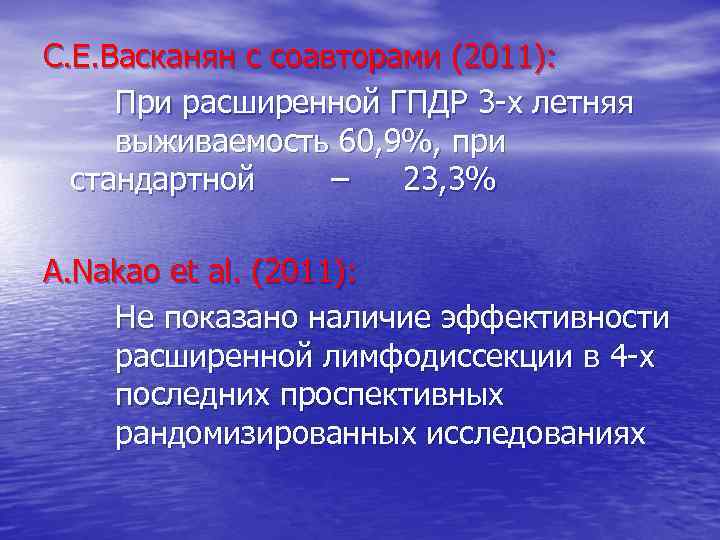

С. Е. Васканян с соавторами (2011): При расширенной ГПДР 3 -х летняя выживаемость 60, 9%, при стандартной – 23, 3% A. Nakao et al. (2011): Не показано наличие эффективности расширенной лимфодиссекции в 4 -х последних проспективных рандомизированных исследованиях